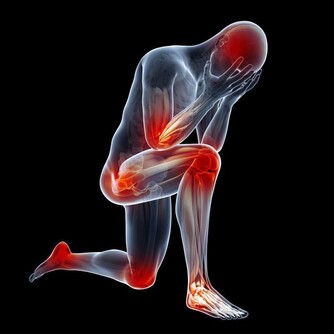

既然是肺癌,為何沒有肺部症狀,反而會是關節痛呢?

有文獻報導認為,癌細胞在增生分化過程中,會引起生長激素分泌異常。

大量的生長激素會刺激骨關節異常增生,侵犯膝、踝、腕等大關節,出現腫脹、疼痛等症狀。

據報導,老年人肺癌合併關節痛的發生率約佔10%至20%。

因此,對中、老年人突然逐漸加重的肩臂痛,無論是否伴有呼吸道症狀,

且肩臂痛經牽引或止痛藥治療,只能暫時緩解症狀而不能阻止疼痛進行性加重時,就需高度警惕。